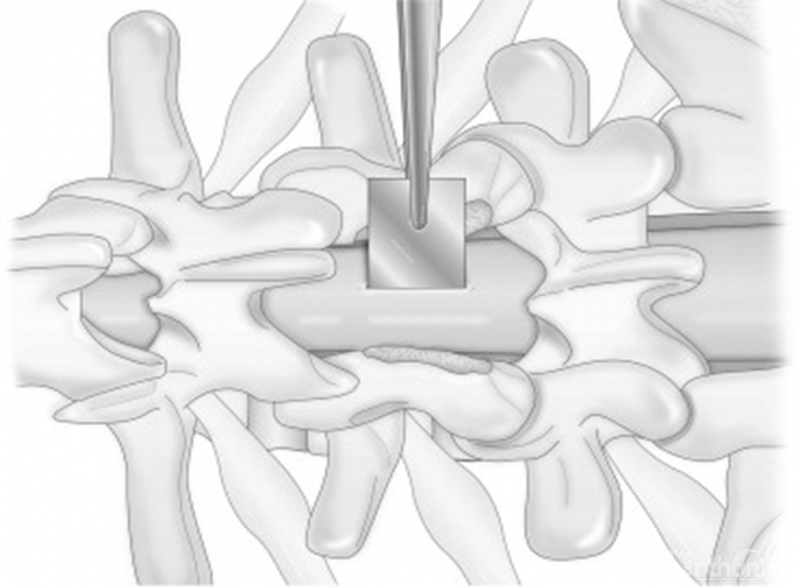

• 在闭合切口的过程中,应尽量选择圆针,减少缝针本身以及缝线切割筋膜的情况;

免打结倒刺线水密闭合深筋膜层,防止脑脊液、血液、组织液等通过深筋膜缝隙渗漏到皮下1,2

免打结倒刺线缝合胸腰筋膜层-高林(西安红会医院)